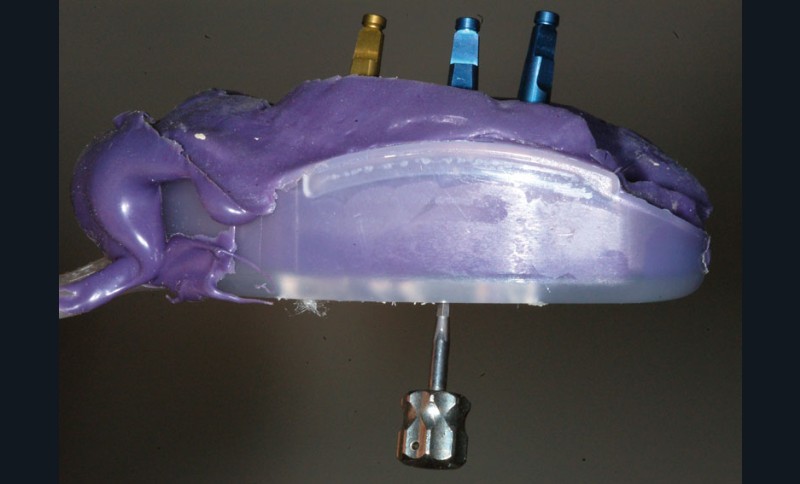

Une fois les transferts pick-up EV® transvissés, le porte-empreinte Tray, fenestré en regard des transferts, est chargé de matériau monophase Impregum™ Penta™ Soft (3M ESPE). Du matériau est déposé autour des transferts à l’aide d’une seringue. Après dévissage des transferts, ces derniers sont emportés dans l’empreinte et les analogues d’implants sont transvissés.

Une fois les transferts pick-up EV® transvissés, le porte-empreinte Tray, fenestré en regard des transferts, est chargé de matériau monophase Impregum™ Penta™ Soft (3M ESPE). Du matériau est déposé autour des transferts à l’aide d’une seringue. Après dévissage des transferts, ces derniers sont emportés dans l’empreinte et les analogues d’implants sont transvissés.

Une fois les transferts pick-up EV® transvissés, le porte-empreinte Tray, fenestré en regard des transferts, est chargé de matériau monophase Impregum™ Penta™ Soft (3M ESPE). Du matériau est déposé autour des transferts à l’aide d’une seringue. Après dévissage des transferts, ces derniers sont emportés dans l’empreinte et les analogues d’implants sont transvissés.

Une fois les transferts pick-up EV® transvissés, le porte-empreinte Tray, fenestré en regard des transferts, est chargé de matériau monophase Impregum™ Penta™ Soft (3M ESPE). Du matériau est déposé autour des transferts à l’aide d’une seringue. Après dévissage des transferts, ces derniers sont emportés dans l’empreinte et les analogues d’implants sont transvissés.

Une fois les transferts pick-up EV® transvissés, le porte-empreinte Tray, fenestré en regard des transferts, est chargé de matériau monophase Impregum™ Penta™ Soft (3M ESPE). Du matériau est déposé autour des transferts à l’aide d’une seringue. Après dévissage des transferts, ces derniers sont emportés dans l’empreinte et les analogues d’implants sont transvissés.